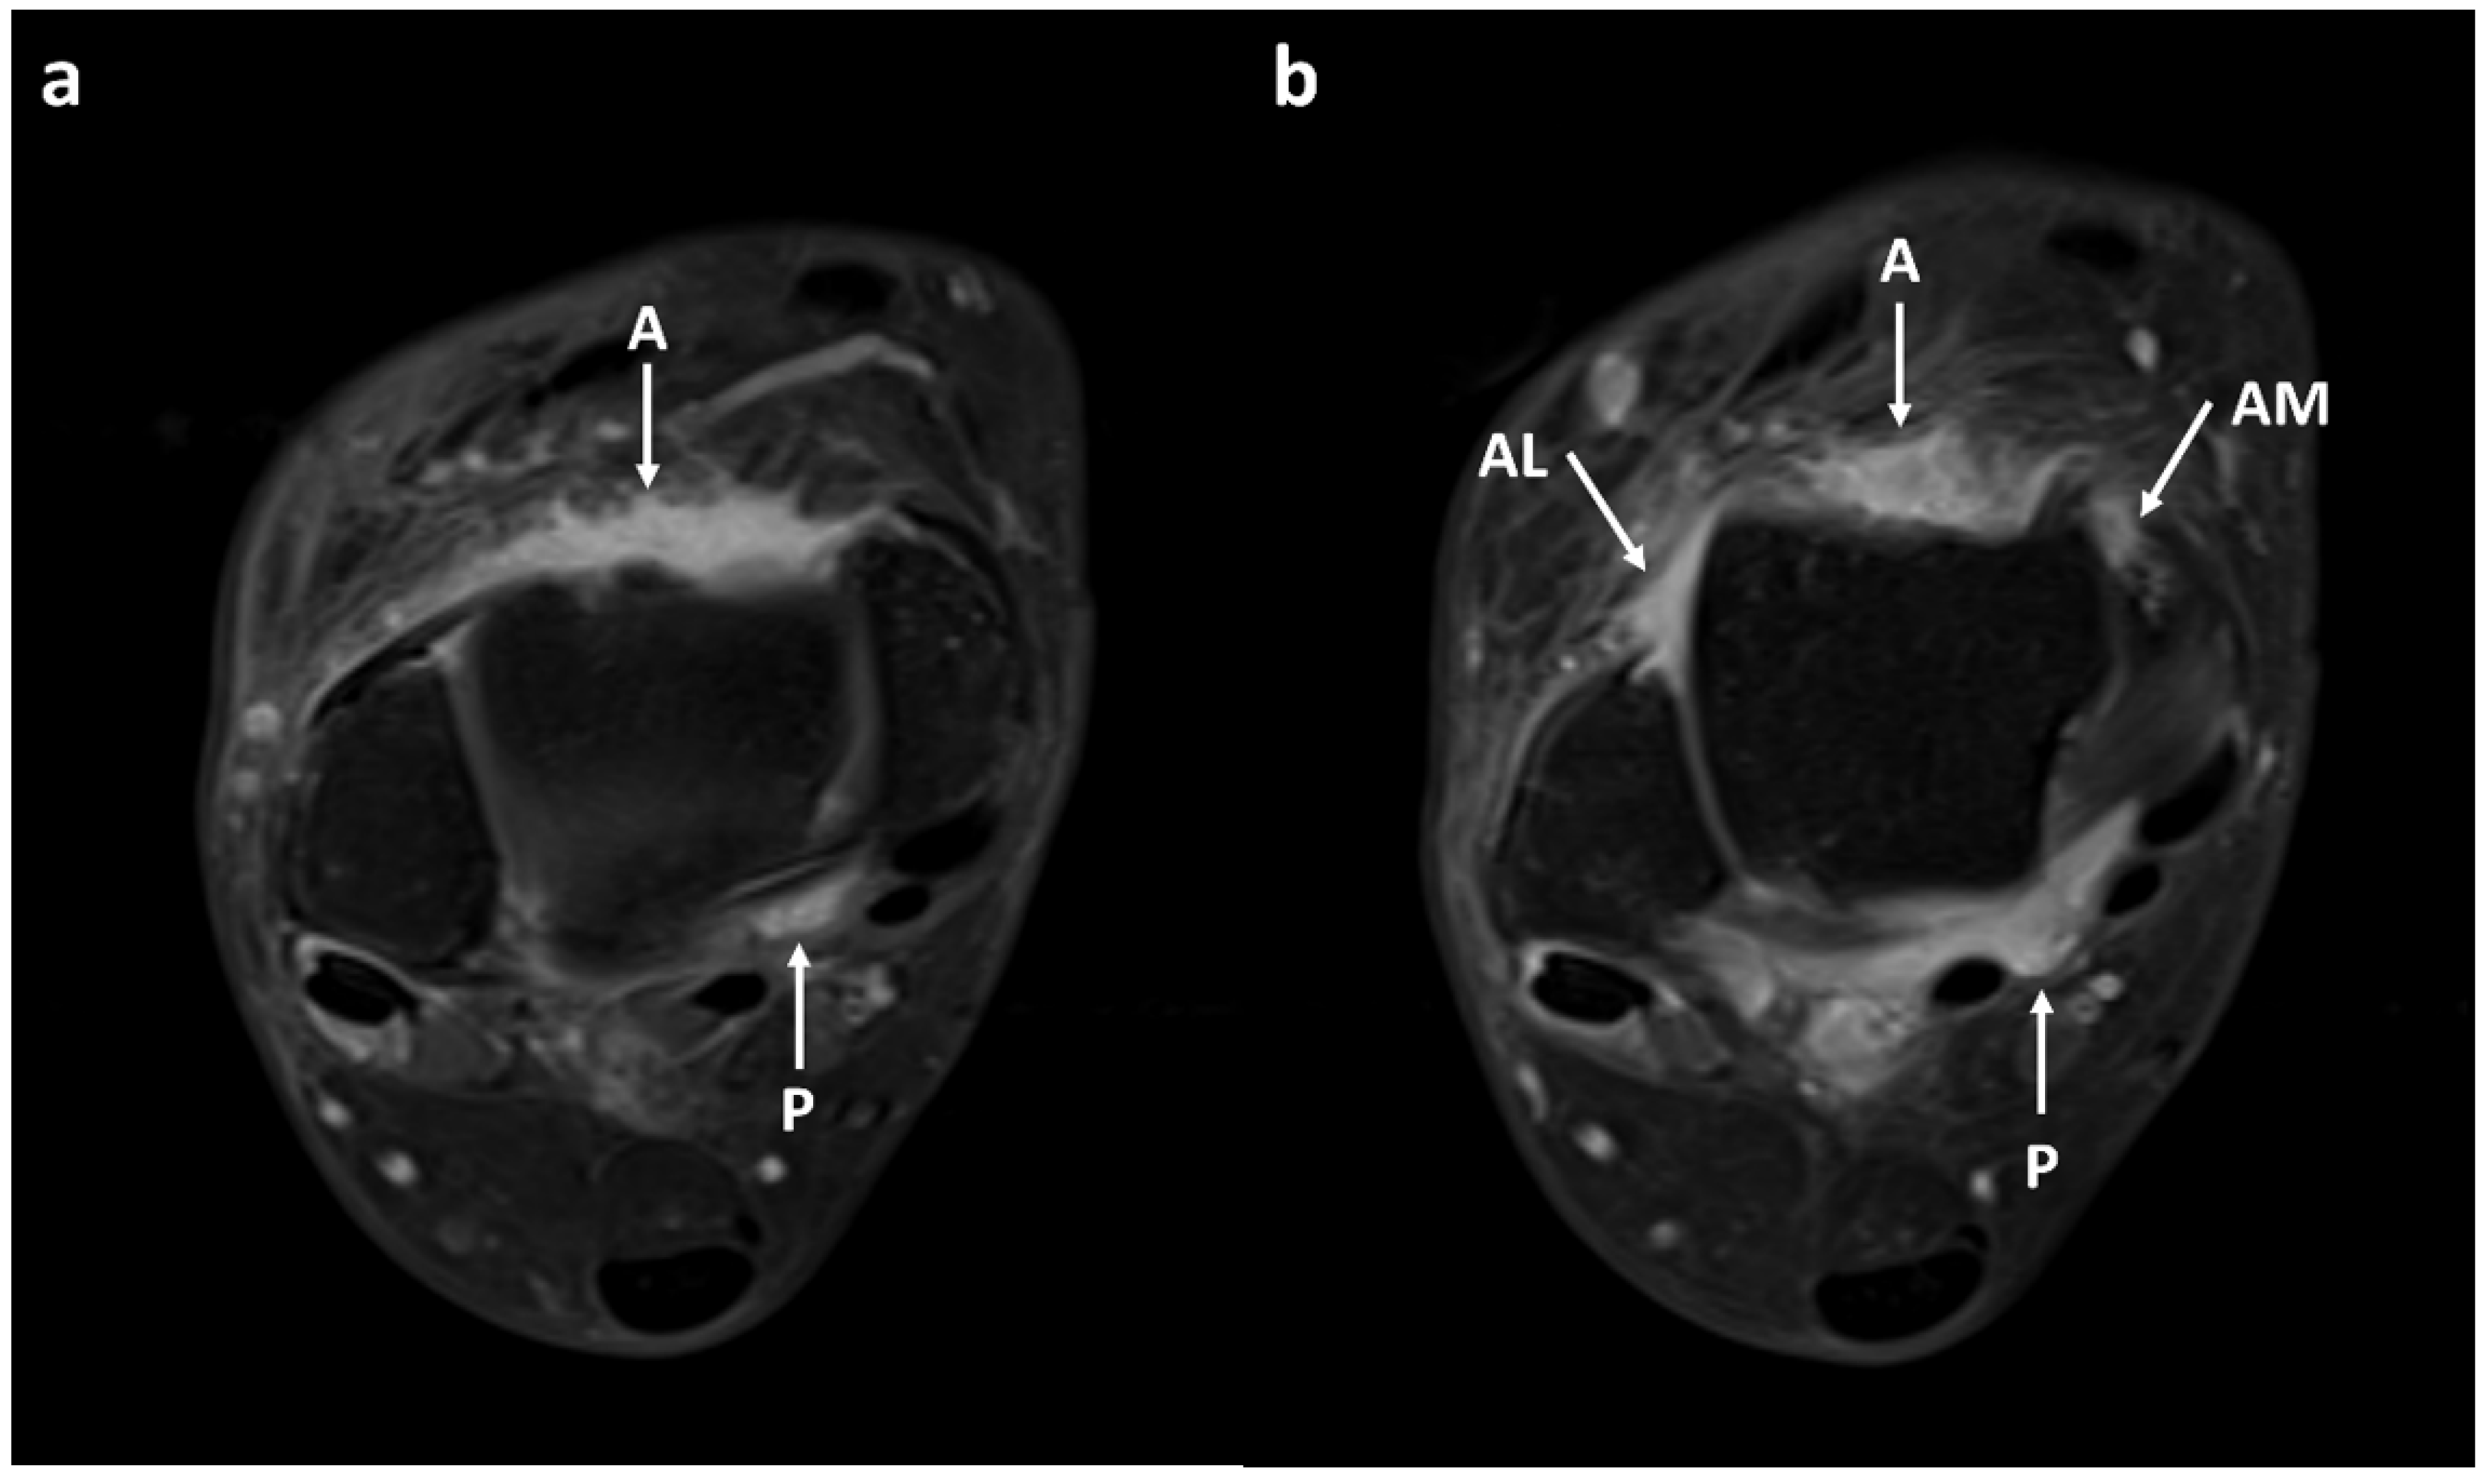

3.2. Synovial Visibility on FLAIR-FS and CE-T1 Images